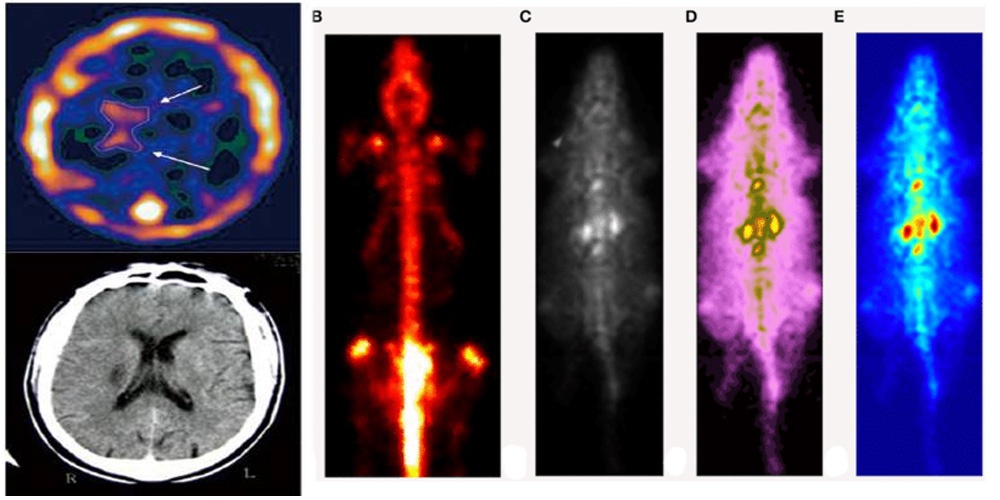

Одним из таких методов является позитронная эмиссионная томография, или ПЭТ (ПЭТ-скан). Прибор, используемый для этих целей, является по сути обыкновенным детектором радиоактивного распада, и может быть объединен с блоком КТ для гибридной визуализации.

Существует другой схожий метод, основанный на введение радиотрейсера – однофотонная эмиссионная компьютерная томография, ОФЭКТ (SPECT). В отличие от ПЭТ, где детектор определяет позитроны, в SPECT трейсер испускает гамма-лучи. В качестве трейсера у людей используют Ceretec – органический комплекс, содержащий технеций-99.

SPECT обладает заметно малым разрешением (около 1 см), но поскольку трейсеры для медицинского применения у человека циркулируют в кровотоке, не попадая в ткани, он пригоден для обнаружения ишемии, онкологических процессов и других аномалий, связанных с кровообращением. Все же, метод в большей степени используется для визуализации сердца, а не мозга. Его основное преимущество – он существенно более доступен, чем ПЭТ, при этом обладая хорошим функционально-диагностическим потенциалом.